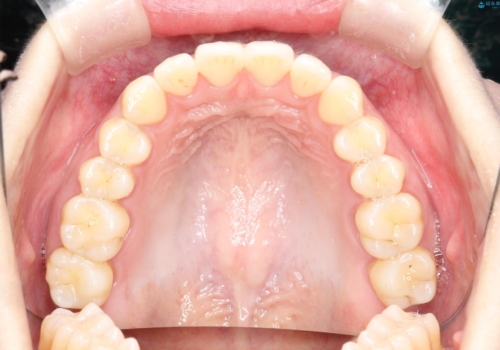

見た目、嚙み合わせ及び、治療期間や施術内容に大変ご満足いただきました。